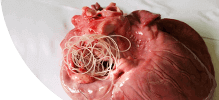

Parazil - ПАРАЗИТЛАРНИ ЙЎҚ ҚИЛАДИ ВА БИР КУРСДА ҚАЙТА ИНФЕКЦИЯ БЎЛИШДАН ҲИМОЯ ҚИЛАДИ!

- Паразитларни фалаж қилади ва тухумларини 48 соат ичида йўқ қилади

- У танадан ажралиб, 2-3 ҳафта ичида танадан чиқариб ташланади